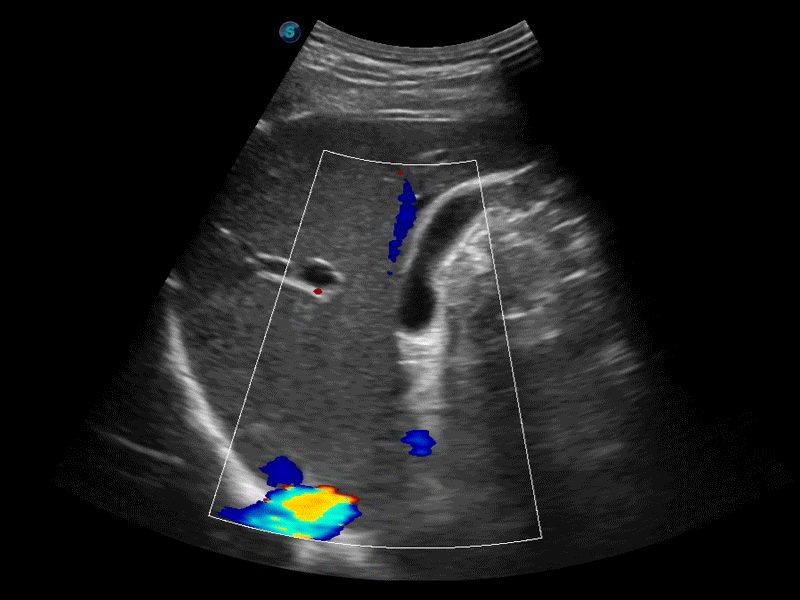

通过色彩血流和实时宽景相结合,可观察到完整的静脉或动脉的血流,方便医生检查。实时扫查过程中,如有任何操作失误也可以很容易地进行回扫擦除,而不会中断扫查。